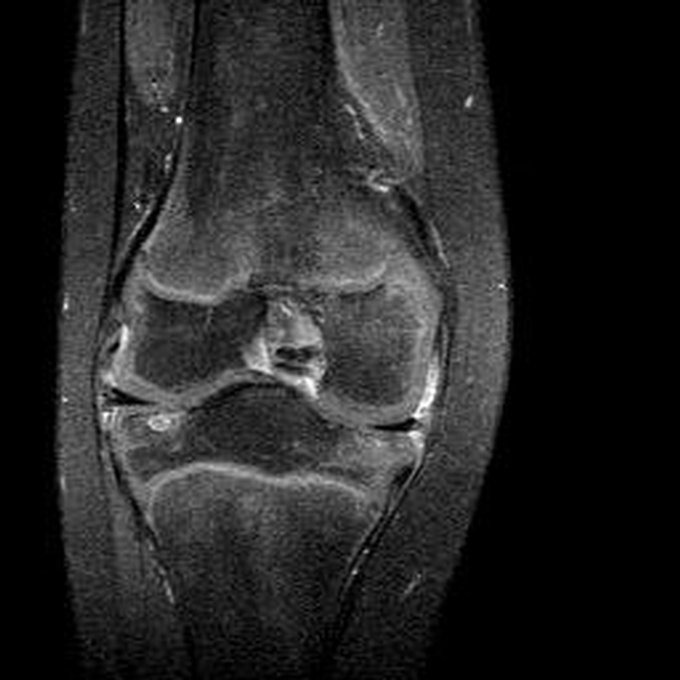

Haemophiliearthropathie bei Haemophilie A.

Arthropathia ARC123 Haemophiliearthropathie bei Haemophilie A.

MRT (high)